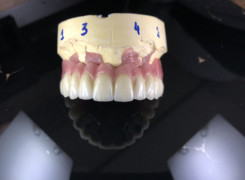

Pan Ryszard trafił do Naszego Gabinetu z jasno sprecyzowanym oczekiwaniem. Miał 84 lata i chciał odzyskać możliwość swobodnego spożywania posiłków oraz poprawienia sobie komfortu życia a także prosił aby przywrócić mu piękny uśmiech jakim cieszył się przed laty. Już na początku pierwszej rozmowy zastrzegł, że interesuje go wyłączenie rozwiązanie uzupełnieniem protetycznym stałym. Nie miał zamiaru użytkować żadnych protez ruchomych. Mając na uwadze powyższe wykonaliśmy Panu Ryszardowi zdjęcie pantomograficzne oraz badanie tomograficzne szczęki i żuchwy na postawie których zapanowywaliśmy Pacjentowi optymalne rozwiązanie – stałe uzupełnienie protetyczne w postaci 28 koron cyrkonowych zamontowanych do dwóch belek cyrkonowych które będą przymocowane do 16 implantów w konfiguracji 8 wszczepów w szczęcie 8 w żuchwie. Po omówieniu powyższego planu przystąpiliśmy do Wspólnej pracy której efekty w poszczególnych etapach prezentujemy poniżej.